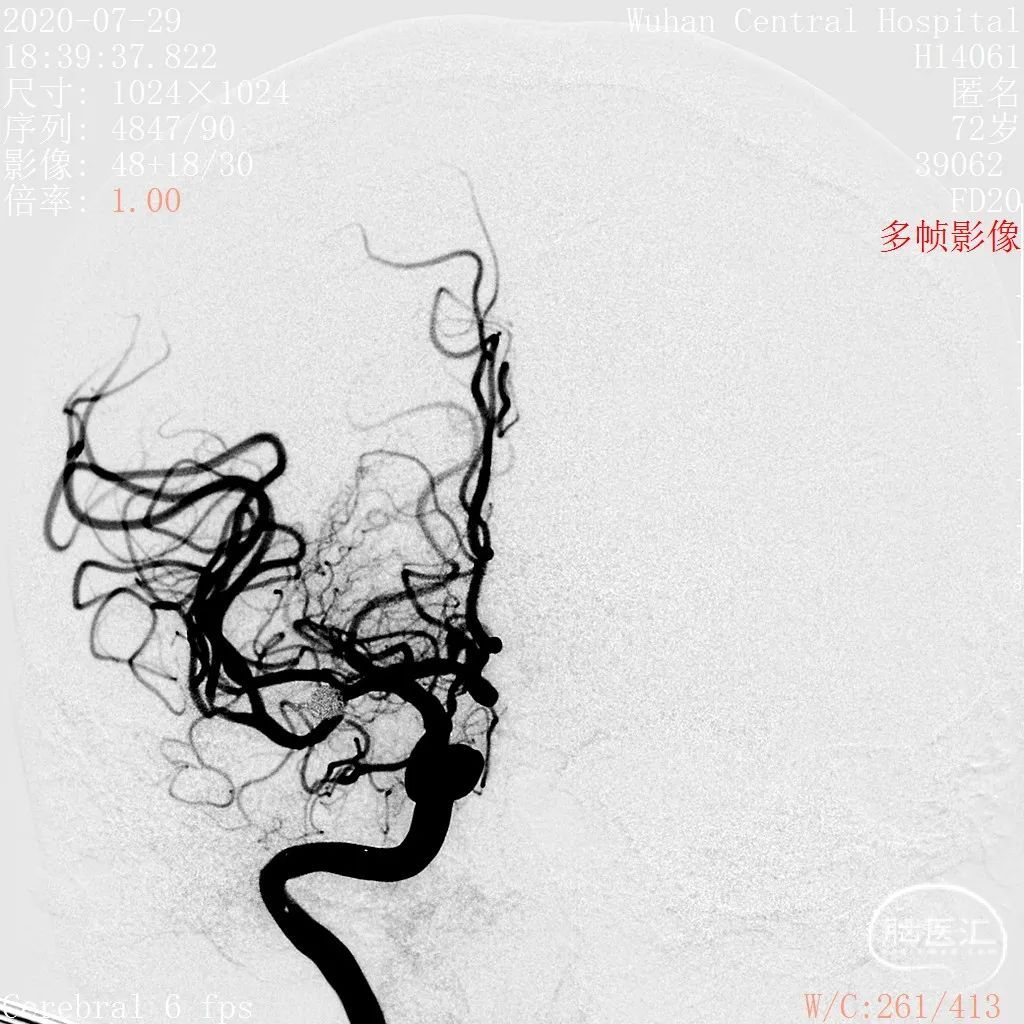

DSA结果:右侧大脑中动脉分叉部动脉瘤,约5.3*5.2mm,颈宽约2.9mm,形态囊状。

术前影像

DSA 2020-07-29